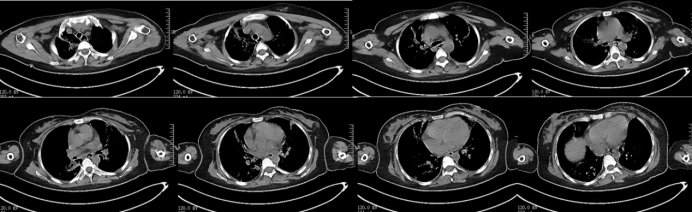

928日外出复查胸部CT:双肺渗出和实变明显吸收改善(图10,图11)

图片

10  复查胸部CT(2024-09-29)

11  患者胸部CT对比